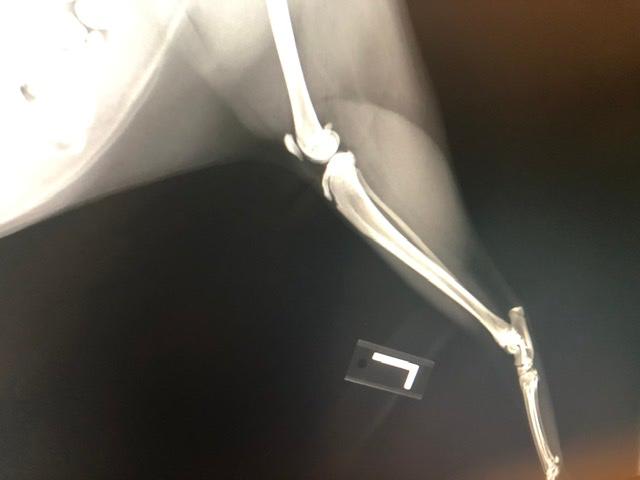

Our cat has been limping for days we took him for X-rays and they want him to see an orthopedic surgeon. Is there anyway you can tell me what is wrong and what the estimated cost or what the procedure would be?

How old is he? If he is past 1 year old, I would be concerned that he may have a fracture of the tibial crest. That is the large bone below the knee. The hips also don't look 100% normal. Without doing an exam on him myself and knowing exactly where he is painful, it is difficult for me to just look at the radiographs and give you a diagnosis. Also, every veterinary surgeon charges differently for different procedures and it is also very depending on location and cost of living. My advice to you would be to go in for the consultation with the surgeon so they can give you more details on what is wrong with him and the best course of treatment. Be sure to ask for estimates for the procedure and if you cannot afford what they are recommending, simply ask what the next best, more affordable option would be. Cats are quite resilient and sometimes they can heal with strict confinement, but I would see what the surgeon thinks. I hope this helps and he starts to feel better soon.